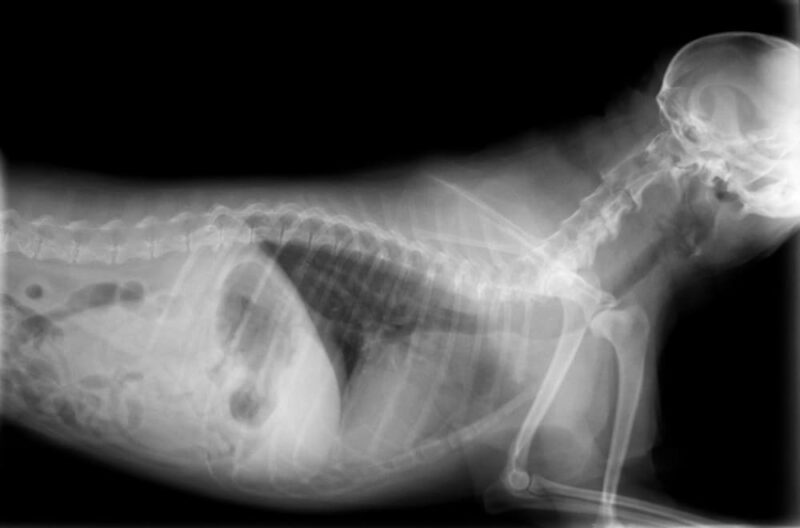

Xrays in Dogs Altas Palmas Animal Clinic

Xrays in Dogs Altas Palmas Animal Clinic How Much Does It Cost To Get My Dog X Rayed Where you choose to take your dog can play a big part in determining the cost. The procedure itself is relatively inexpensive, minimally invasive, and painless for your pet, but it requires the animal to remain still for an extended period of time. However, the range can be between $75 and $500, depending on numerous factors. There is a wide. How Much Does It Cost To Get My Dog X Rayed.